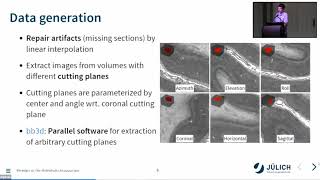

3D reconstruction and visualization techniques for primate brains

3D reconstruction and visualization techniques for primate brains 3D reconstruction and analysis of the macaque brain from histological slices

3D reconstruction and analysis of the macaque brain from histological slices Thomas Funck: 3D reconstruction

Thomas Funck: 3D reconstruction MRI guided hierarchical sectioning and stitching of brain blocks for alignment

MRI guided hierarchical sectioning and stitching of brain blocks for alignment Christian Schiffer: Perspectives of High-Resolution 3D Reconstruction